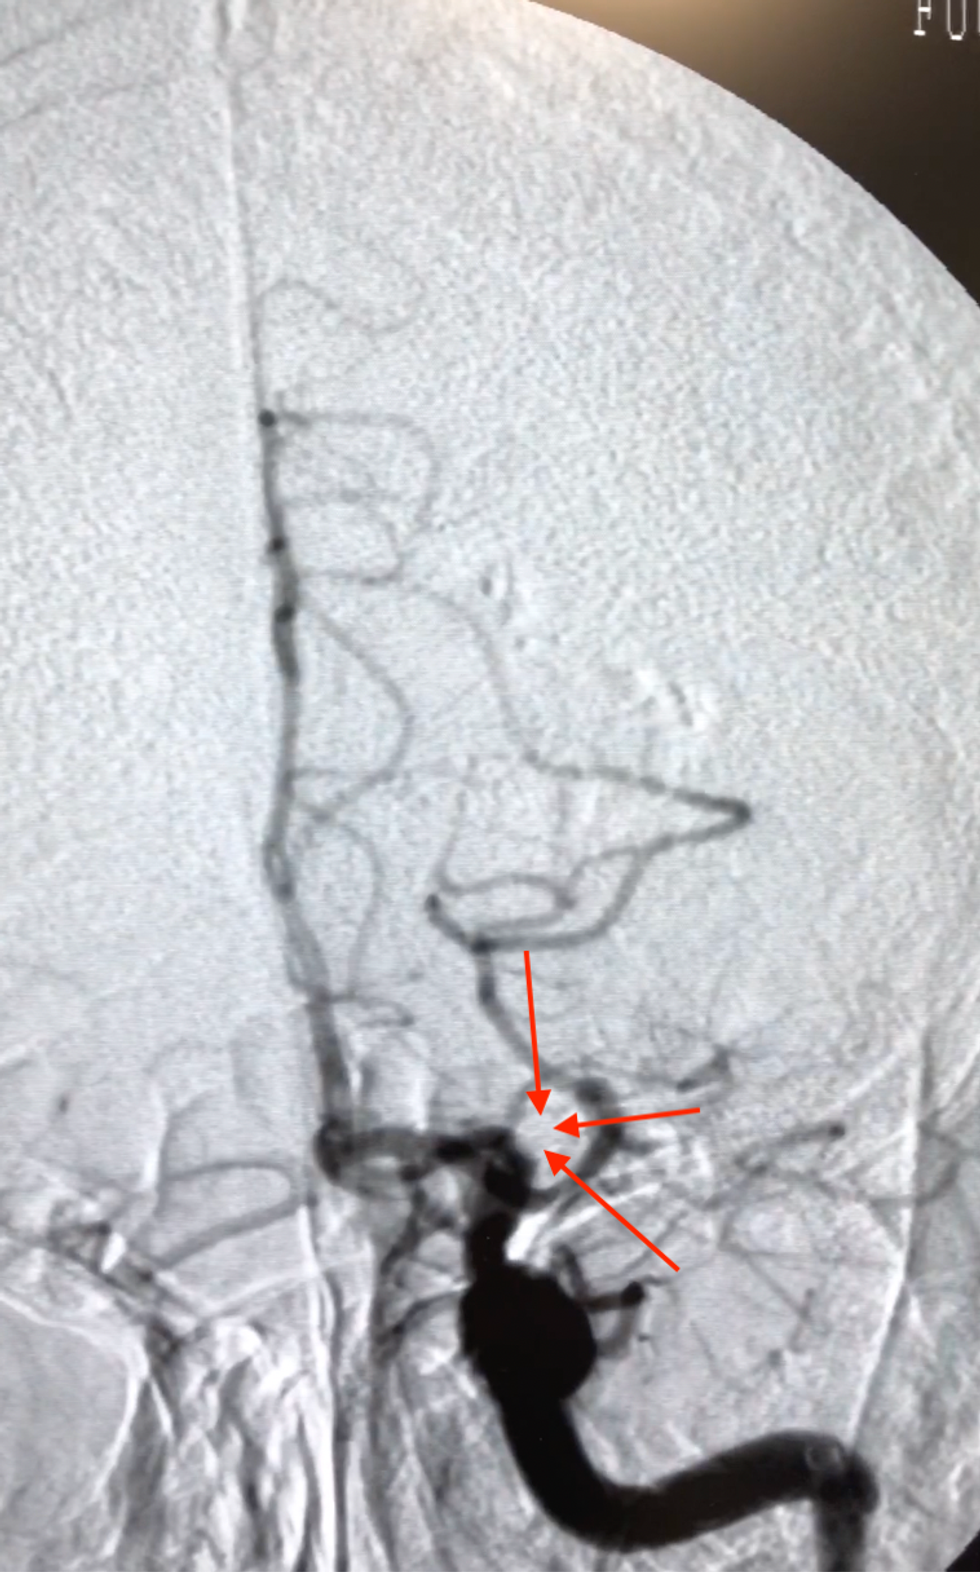

Pas rekanalizimit, në imazhet e ADS prezantohet ACM djathtas e rekanalizuar në tërësi

Edhe pse është rekanalizuar në tërësi, funksionet nuk iu kthyen menjëherë, por me angazhimin e saj në terapi fizikale, rezultatet e arritura vetëm sa janë shtuar.

Në ADS imazhe konstatohet mbyllja e arteries trunore të mesme djathtas (ACM).

Okludim – mbyllje e arteries së mesme trunore djathtas (ACM)

Realizohet metoda e kombinuar e trombektomisë mekanike: aspirimi dhe përdorimi i stent retrivier (stentit tërheqës).

Arrihet rihapja – rekanalizimi i arteries së mesme trurore djathtas dhe rivendoshet qarkullimi i plotë i gjakut në tru.

Në imazhet e ADS pas realizimit të trombektomisë, konfirmohet rihapja dhe rivendosja e qarkullimit të gjakut në arterien e mesme trunore djathtas